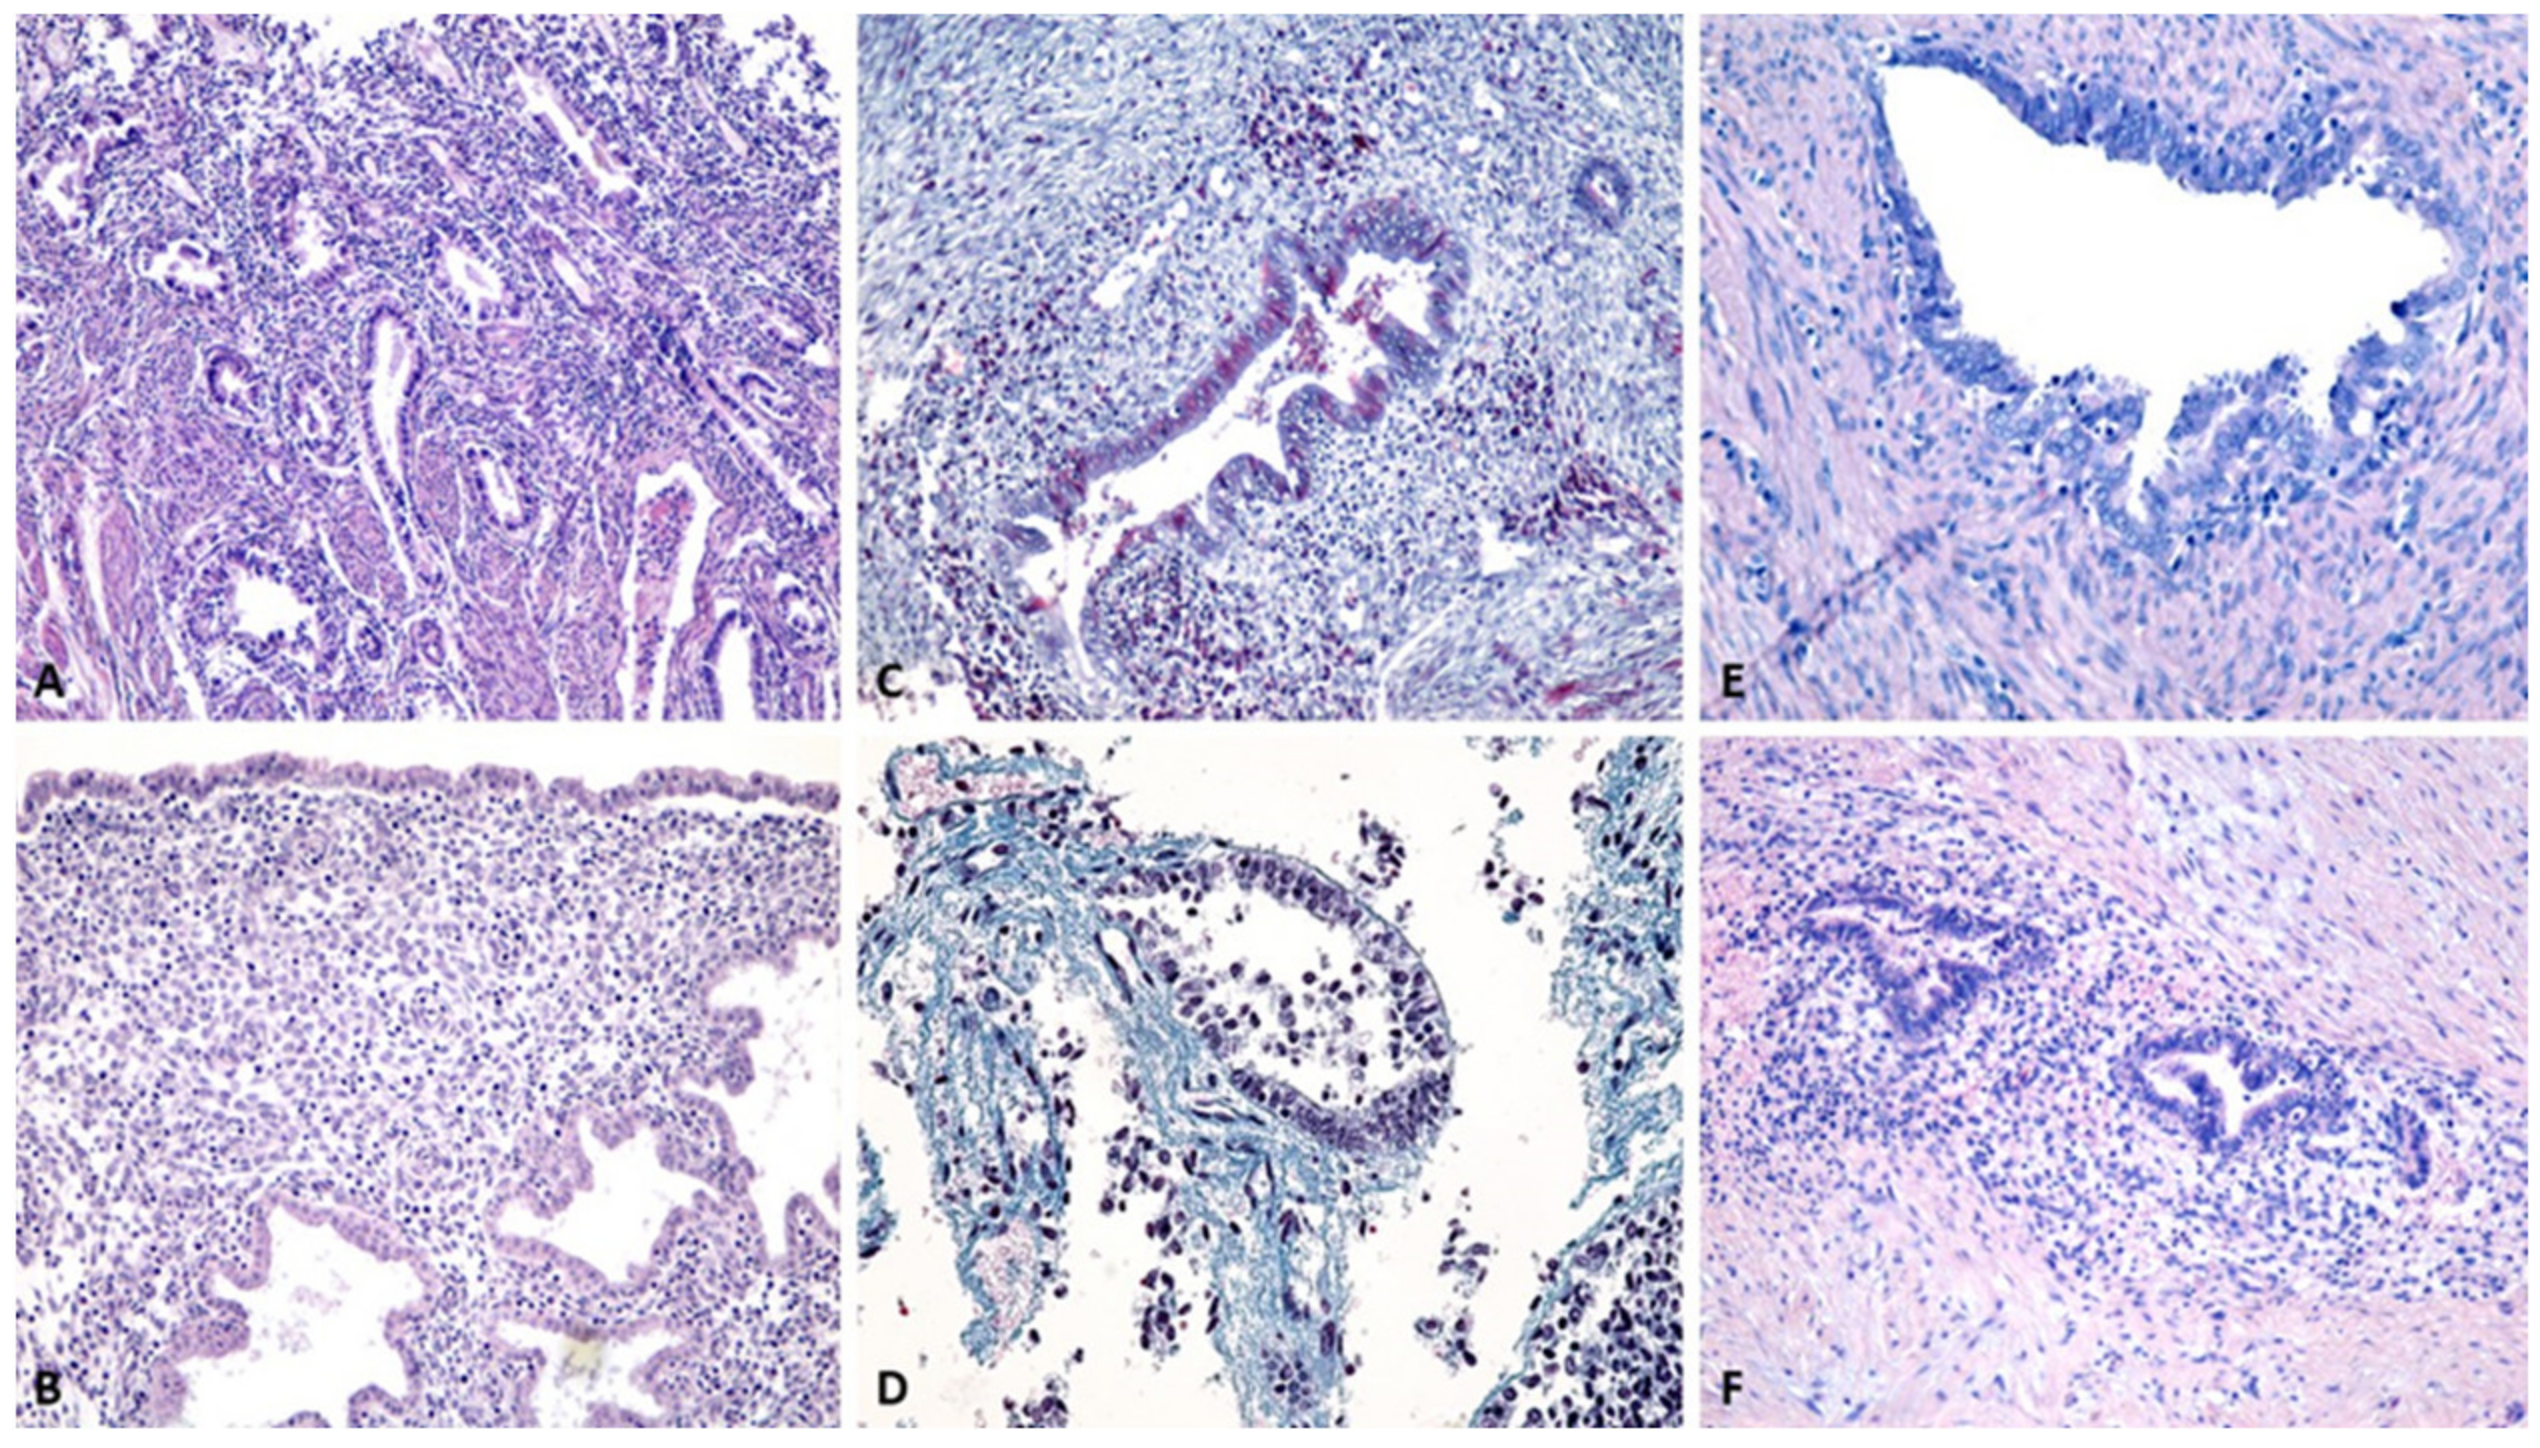

3.2. Evaluation by Classical Histopathological Staining Methods

3.3. Histopathological Characterization by Single Immunohistochemistry

3.3.1. Cytokeratin Reactivity Analysis

3.3.2. Hormone Receptor Reactivity Analysis

3.4. Stromal Vascularization Analysis

3.5. Analysis of Cell Proliferation and Involvement of Tumor Proteins

3.6. Analysis of Perilesional Stromal Inflammatory Changes

3.7. Histopathological Characterization by a Novel, Multiple Immunohistochemical Labeling Technique